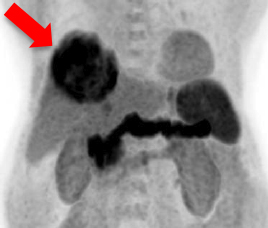

- 治疗前双示踪剂正电子/电脑双融扫描

- 肝脏肿瘤因代谢高丶体积大而不适宜手术治疗

- 甲胎蛋白水平是2269 ng/ml

C-11 Acetate F-18 FDG